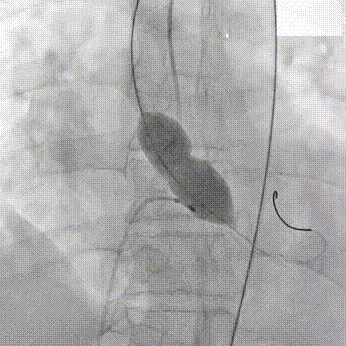

主动脉根部造影

TaurusOne AV23mm瓣膜瓣下3-4mm 工作位造影